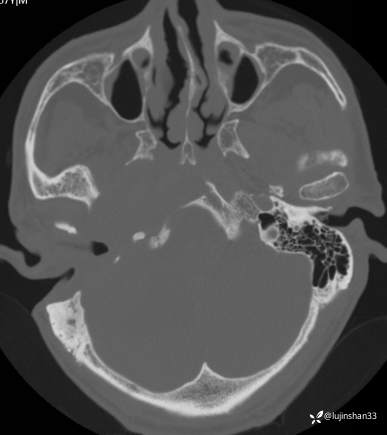

(2023-05-29 16:07,本院)CT颅脑:1、右侧颞骨全切除术后改变,术区见气体密度影,瘘管形成可能;术区多发软组织影,不完全除外炎性改变可能。2、左侧颞骨CT平扫未见明显异常。